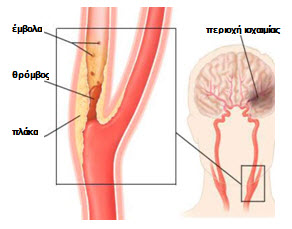

Είναι η νόσος που χαρακτηρίζεται από την δημιουργία αθηρωματικής πλάκας στον καρωτιδικό διχασμό που έχει σαν συνέπεια την στένωση των αγγείων. Σπάνια η στένωση μπορεί να μην οφείλεται σε αθηρωματική βλάβη αλλά σε άλλα αίτια (π.χ. ινομϋική δυσπλασία)

Όταν η πλάκα προκαλεί μεγάλη στένωση αυξάνει η πιθανότητα να σχηματισθεί θρόμβος αίματος ή να ραγεί η αθηρωματική πλάκα με αποτέλεσμα να αποσπασθούν τμήματα του θρόμβου ή της πλάκας που λέγονται έμβολα και στη συνέχεια να αποφράξουν αρτηρίες του εγκεφάλου και να προκαλέσουν ισχαιμικό εγκεφαλικό επεισόδιο.